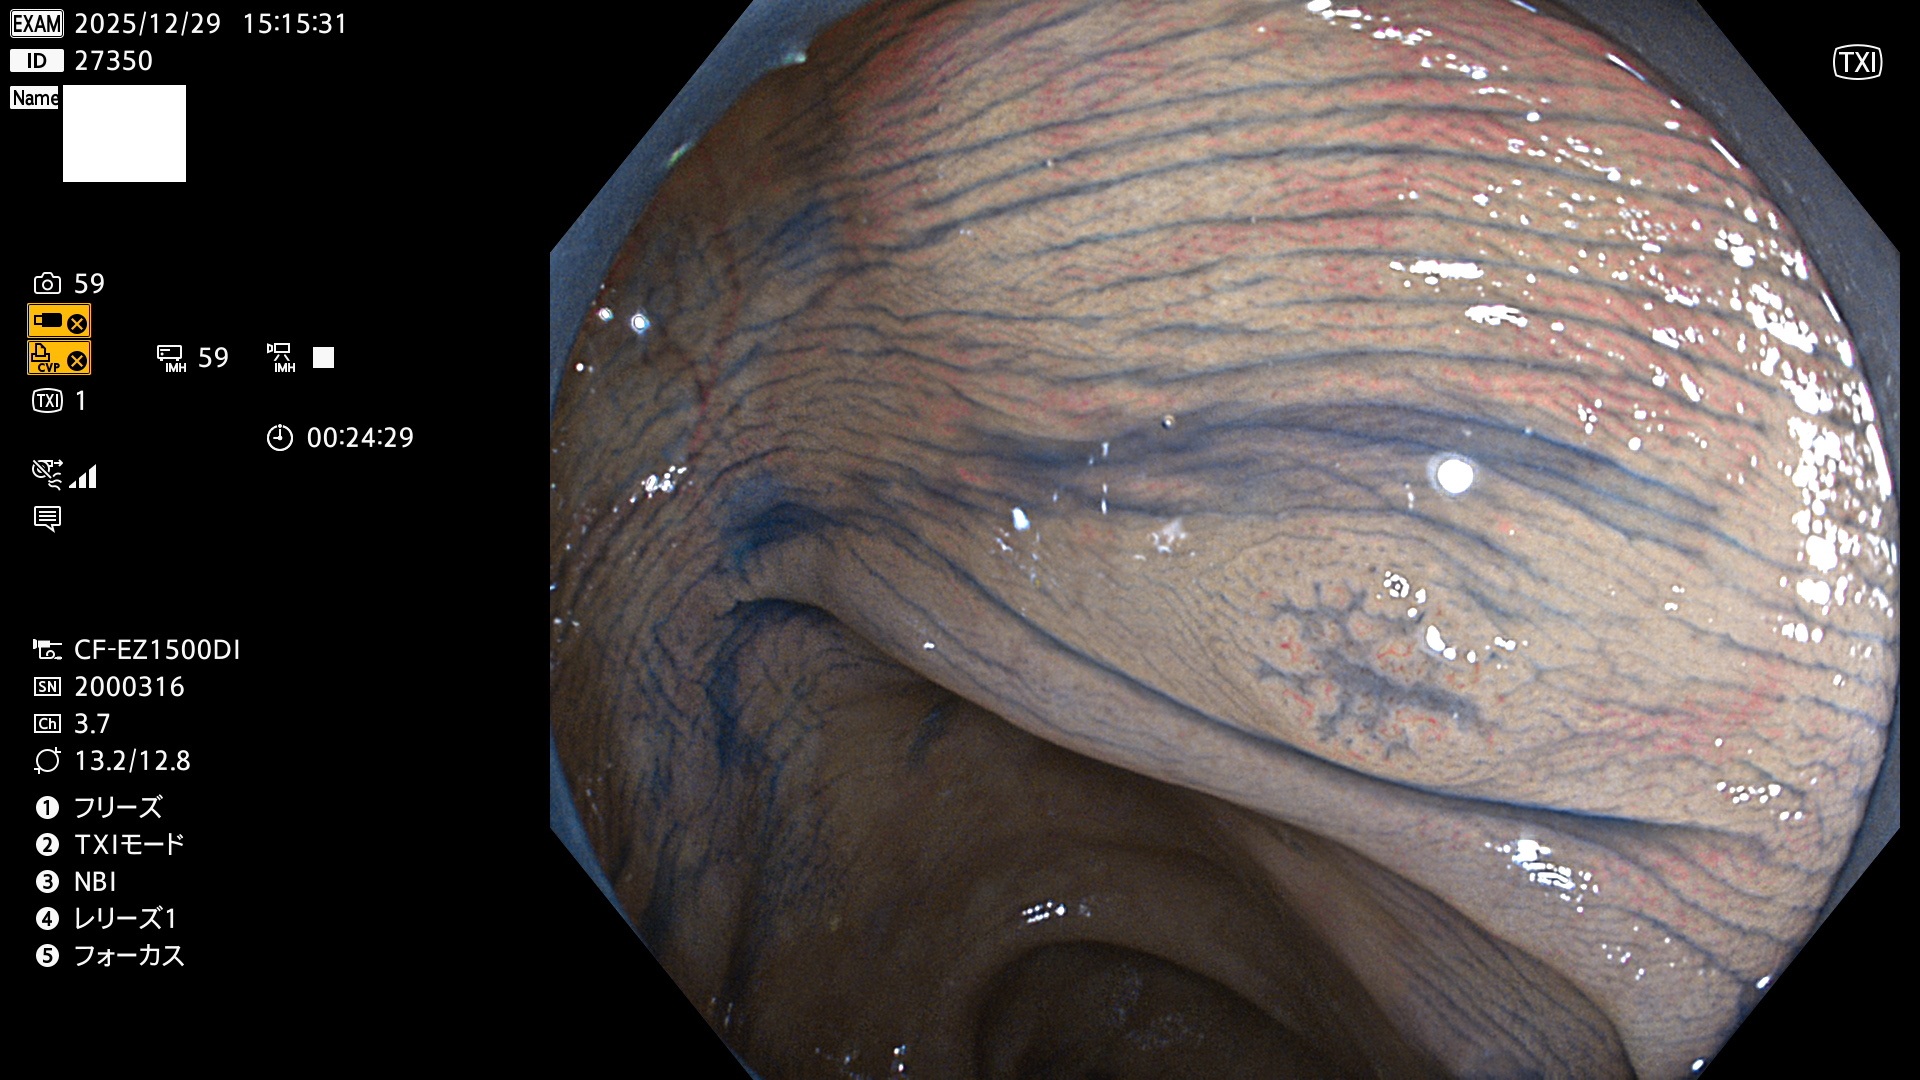

完全に平坦な物をUb、陥凹している物をUcと呼びます。Ubは認識が困難で、Ucはびらん(炎症)と紛らわしいために見落とされやすく、「内視鏡後・大腸癌」の原因になります。

専門的)Uc=De Novo癌? 内視鏡の解像度が低かった時代、このような説もありました。しかし今日の高精度内視鏡では良性の微小なUc型腺腫(APC遺伝子異常の腺腫)が日常的に見つかります。Ucこそが多段階発癌(Adenoma-Carcinoma Sequence)のMain Routeです。

毎週の検査(木・金・土・日)に発見されたUbとUc型・腺腫を、その週の日曜の夜にUPし1週間、提示します。

2025年12月18日〜12月29日の8日間(80件)13個 (Uc_ADR=13個/80人=16%)